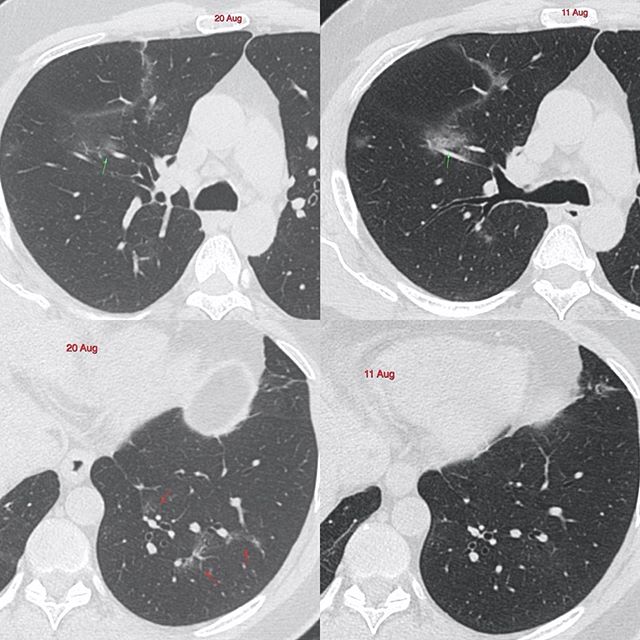

Then we have this 42-years old man with two scans done 9 days apart, who was mildly symptomatic at the time of the first scan and is asymptomatic at the time of the 2nd scan. The upper lobe lesions seen on the first scan have improved (green arrows), but there are new lesions in both lower lobes, especially the left (red arrows).

So is this progressive disease? Or is it more likely that the lesions increased immediately after the first CT and have settled and this is now the residue of that increase? It is not an easy distinction to make radiologically, though clinically if the patient is fine, then these CT scan appearances probably don’t matter.